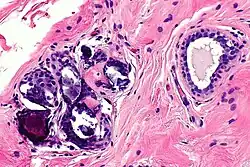

Around 1.5 million women have breast implant surgeries per year,[15] but the side effects can be severe and cause irreversible damage to the patient's body. The most well-known side effects are foreign body sensation, calcification, fat cell necrosis, capsular construction, rupture, cysts and some fat cells leaving the implanted area.

In most cases, calcification and cysts are the biggest threat of breast augmentation surgery. Fat stem cells that fail to pick up a new blood supply will die and be removed from the body by immune cells. However, if they are missed, the cluster will lead to calcification and cyst formation. These are visible on the breast as lump sometimes and are more dangerous when these dead cells are detected as cancer cells, which hinders an accurate diagnosis of breast cancer. The calcified tissue will be diagnosed as a benign cancer and not cause any harm. However, if the tissue is severely damaged the entire breast needs to be removed. Once a patient is diagnosed with breast implant calcification, regular mammograms should be done to monitor the possible cancer development.[16]